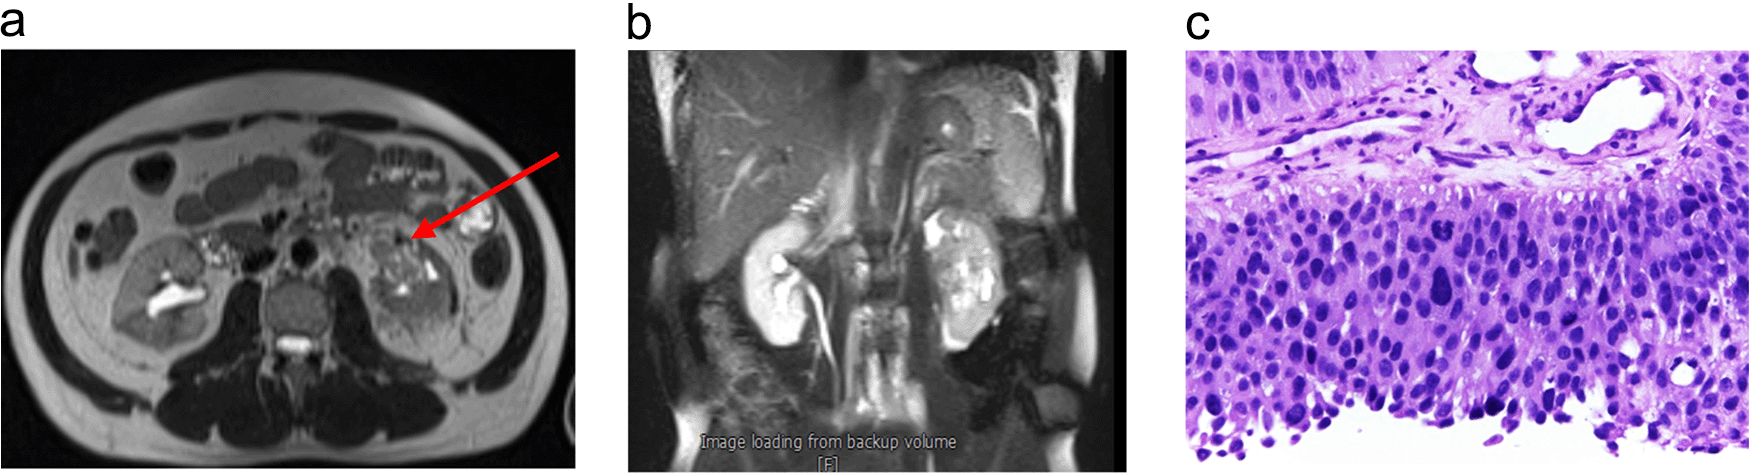

The patient was scheduled for adjuvant chemotherapy but was delayed due to the complaint of left abdominal fullness two months after the procedure. Ultrasound examination showed bilateral hydronephrosis with the left kidney being more severe. An abdominal MRI with contrast was performed (Figure 3a). Furthermore, left nephrostomy and biopsy were conducted and pathology workup showed papillary arranged tumor mass. From diagnostic workup, the patient was diagnosed with left UTUC cT4N0M1 in renal pyelum (Figure 3b).

(a) Abdominal magnetic resonance imaging (MRI) with Gadobutrol 5 ml contrast, shown hyperintense lesions were seen on T1-T2WI and FS on the left intrapelviocalyceal and extracapsular perirenal, which were enhanced after the contrast was administered. (b) High-grade infiltrative urothelial carcinoma. (c) The picture shows papillary-arranged tumor mass, Hematoxylin and Eosin (H&E) stain 400×.